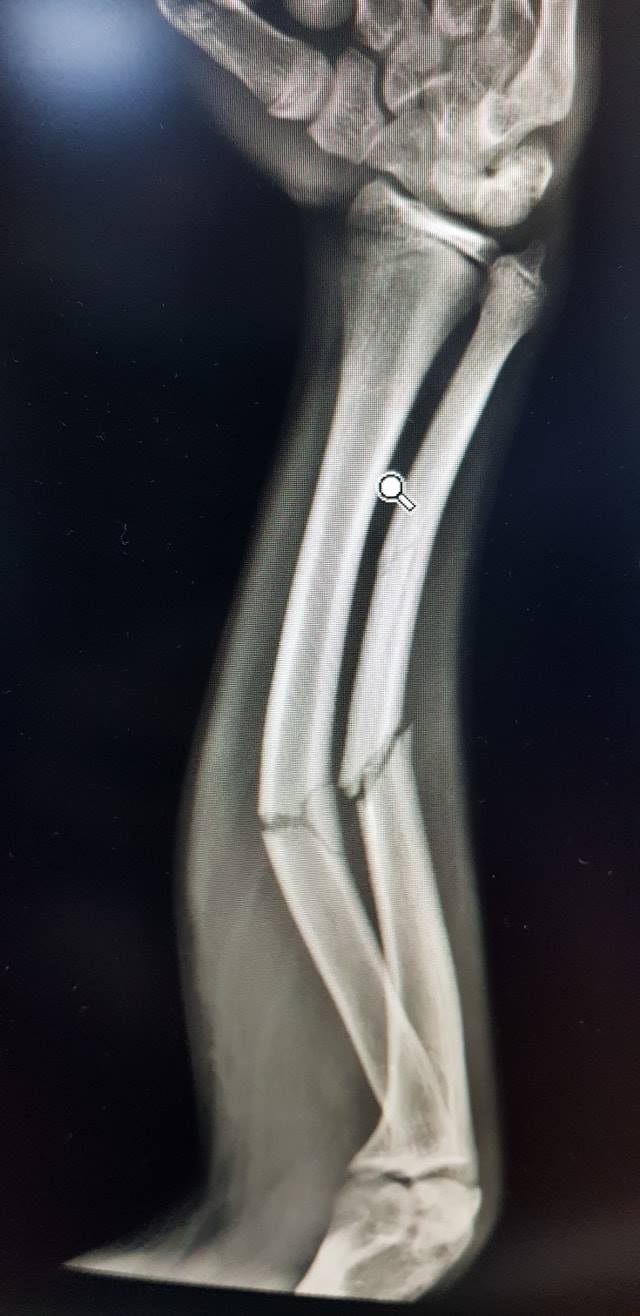

كافة انواع الكسور وعلاجها